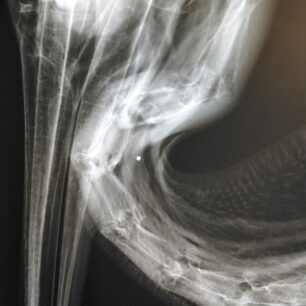

Παρά τις προσπάθειες για τη διάσωση του ο αργυροπελεκάνος, που βρέθηκε πυροβολημένος στις 15 Νοεμβρίου από τον γιατρό Αλέξανδρο Οικονομίδη στη λίμνη Κάρλα κοντά στο χωριό Νάματα Λάρισας τελικά κατέληξε και όπως έδειξαν οι ακτινογραφίες στο κορμί του βρέθηκαν σκάγια.

Στις ακτινογραφίες που ελήφθησαν στο ιατρείο του κου Καλτσά φάνηκαν σκάγια. Τα νευρολογικά συμπτώματα του πουλιού, πριν πεθάνει, παραπέμπουν σε πιθανή μολυβδίαση από αυτά.

o οποίος έφθασε λίγο πριν τη διασωλήνωση. σε συνεννόηση πάντα με το Σύλλογο Προστασίας Άγριας Ζωής ΑΝΙΜΑ! Ο Αργυροπελεκάνος βρέθηκε σε άθλια, απισχνασμένη και ιδιαίτερα εξαντλημένη φυσική κατάσταση ενώ μετά από ενδελεχή κλινικοεργαστηριακό έλεγχο βρέθηκε να φέρει σκάγια στην περιοχή του τραχήλου και της φτερούγας! Πολύ πιθανό είναι τα σκάγια να προκάλεσαν τρώση του οισοφάγου και να δημιούργησαν γενικευμένο υποδόριο εμφύσημα αλλά και δηλητήριαση από μόλυβδο! Μέσα στην ατυχία του ζώου αισθάνομαι πολύ τυχερός που έσφιξα στην αγκαλιά μου έναν από τους σπάνιους εκπροσώπους της Άγριας Ζωής και συνέβαλα και εγώ στη διάσωσή του! Βρίσκεται σε στάδιο νοσηλείας και αύριο προωθείται για την ΑΝΙΜΑ!